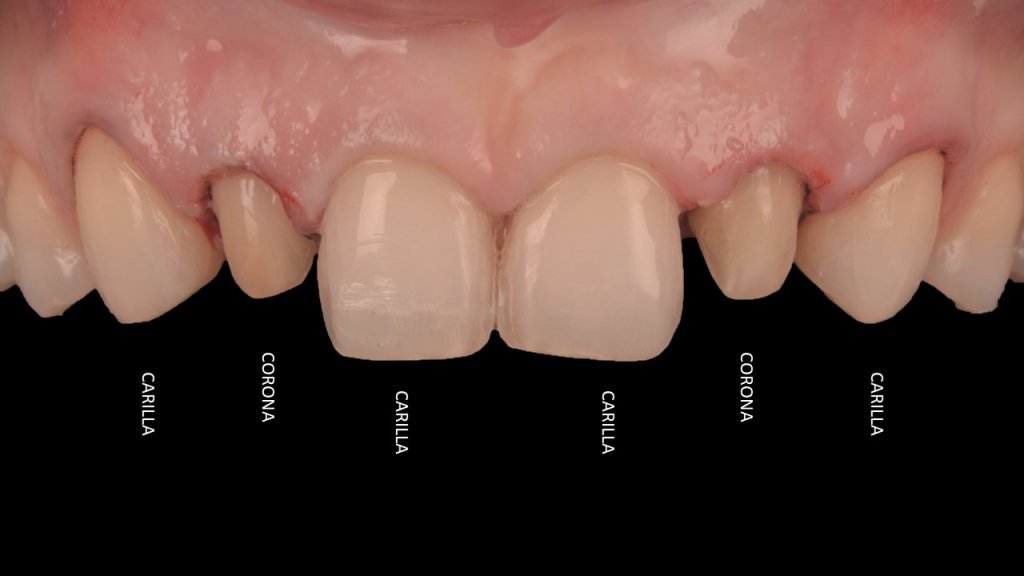

La Re- preparación de las antiguas carillas me deja sin esmalte (un clásico vamos), así que por cuanto no me guste estoy obligado a preparar a coronas. Todo en VERTICAL por supuesto, no hablamos de BOPT en este caso porque me salté la clásica fase de los provisionales.

Y vamos de Azul (NIC TONE) sin linea de terminación, sufrimos el doble..no tenemos donde agarrar el Clamp y sobre todo donde realmente termina la carilla…

Voy siempre de 2 en 2, claramente cemento antes las Coronas, que me ayudaran a «clampar» y luego las carillas. Pero normalmente empiezo con los laterales que están en el medio y suelen robar el espacio a los otros